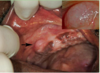

What is this infectious disease?

Describe it

HSV 1- Primary Herpetic

Gingivostomatitis

Ulcer with an erythematous halo (top two arrows). We

also have ulcerations that are irregular in shape on the gingiva

(bottom two arrows).